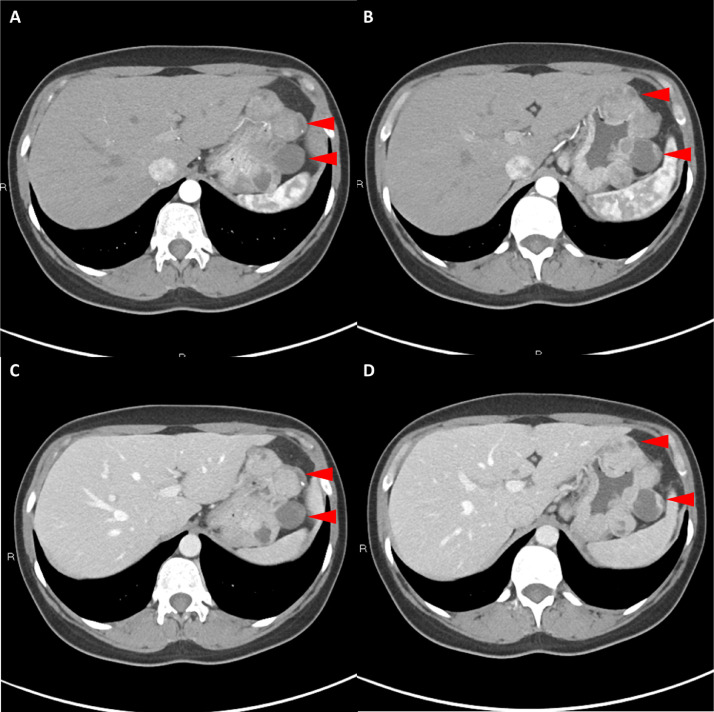

胸部、腹部和骨盆的對比增強(qiáng)動脈和靜脈期 CT 顯示多個(gè)圓形、主要是血管豐富的異質(zhì)腫塊,具有囊性和實(shí)性成分,起源于胃底和胃體(圖 2-4)。 病變部分呈外生結(jié)構(gòu),被認(rèn)為位于粘膜下層。 在頸部多發(fā)同步性副神經(jīng)節(jié)瘤的情況下,賊初的鑒別診斷包括多發(fā)性副神經(jīng)節(jié)瘤、多發(fā)性 GIST 以及轉(zhuǎn)移性疾病。

Fig. 2

圖 2:多發(fā)胃腸道間質(zhì)瘤的軸位 CT 圖像。 (A 和 B)軸位動脈相增強(qiáng) CT 圖像和(C 和 D)軸位靜脈相增強(qiáng) CT 圖像顯示多個(gè)圓形、不均勻、增強(qiáng)的腫塊,具有實(shí)性和囊性成分。 腫塊位于粘膜下,結(jié)構(gòu)呈外生。